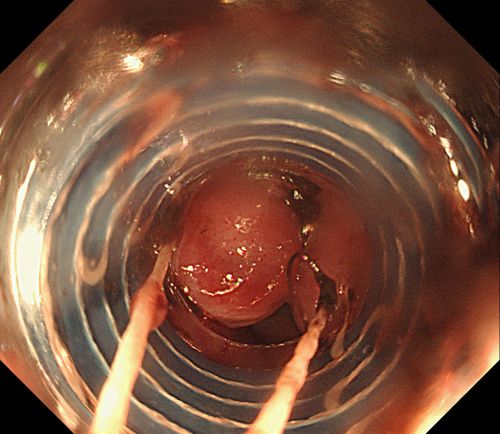

彭娅主任在内镜下小心翼翼抽吸血液清洗血块后,找到“犯罪血管”。

为其实施内镜下食管静脉曲张套扎术。

患者旋即被推入手术室,麻醉三科刘际童主任为其进行气管插管、全麻,保持呼吸道通畅,并进行中心静脉置管等维持血压平稳。综合内科彭娅主任进行胃镜治疗,发现患者重度食管静脉曲张,胃底可见大量血液及血凝块;小心翼翼抽吸血液及清洗血块后,寻找到“犯罪血管”,在内镜下进行食管静脉曲张套扎+硬化剂注射治疗,封闭出血血管。